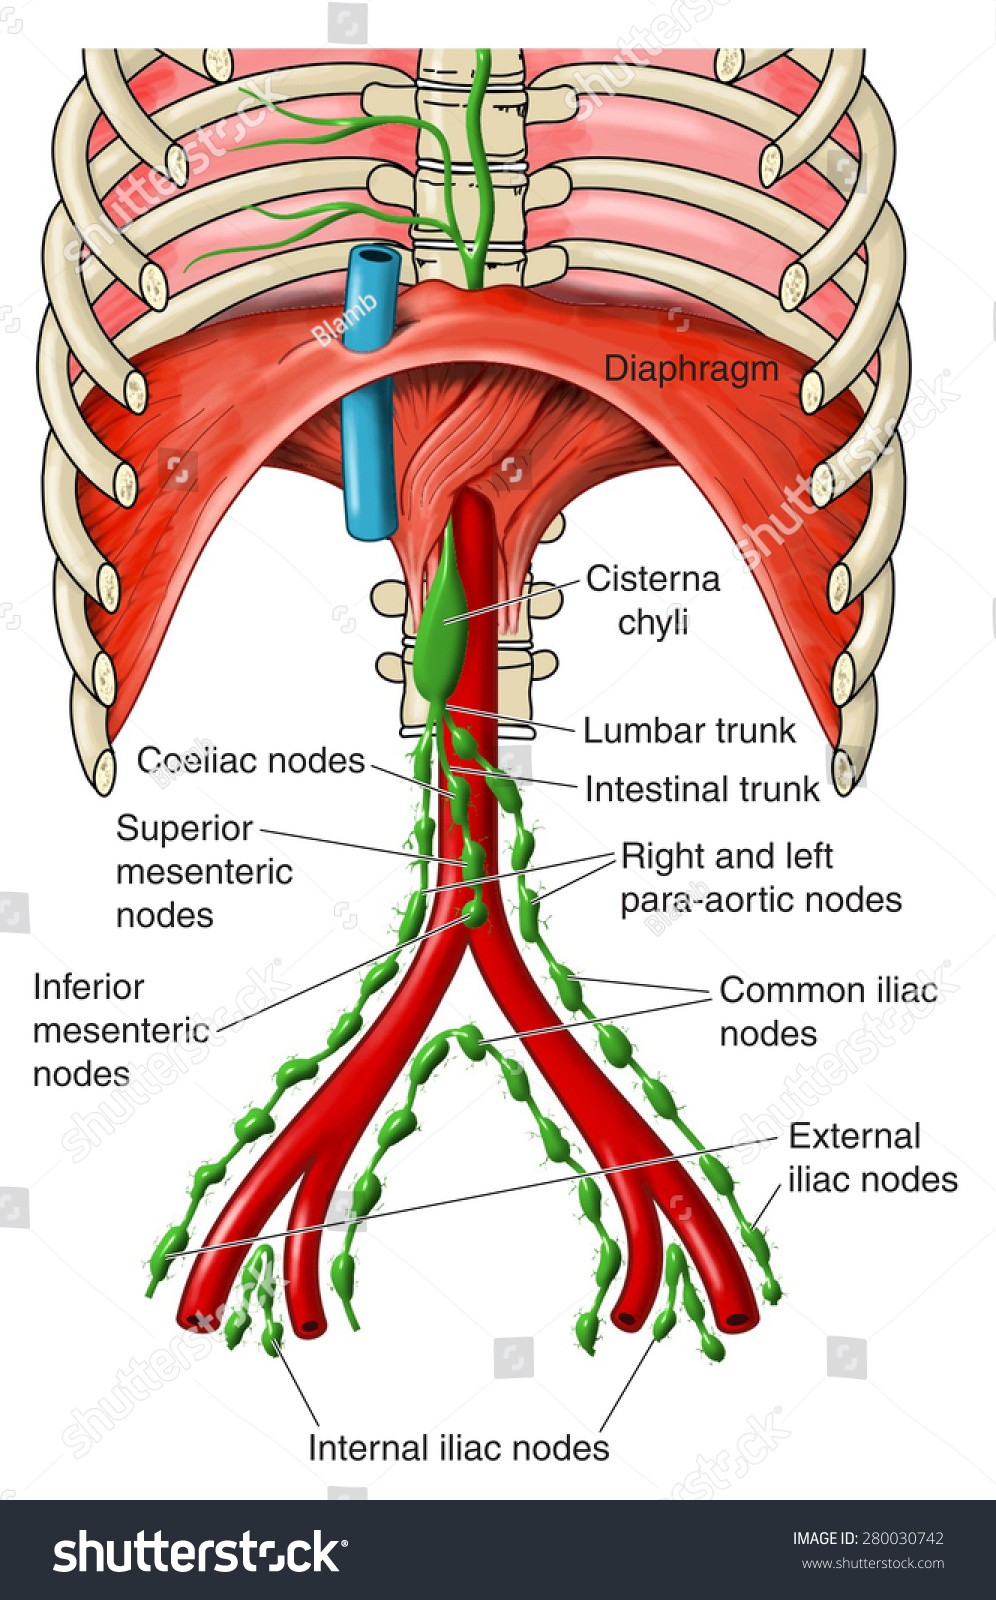

Abdominal Lymph Nodes Iliac Nodes Cisterna Stock Illustration 280030742

www.shutterstock.com

www.shutterstock.com

lymph nodes abdominal cisterna iliac chyli shutterstock stock

PPT - The Lymphatic System PowerPoint Presentation, Free Download - ID

lymph system lymphatic nodes abdomen presentation ppt node mesenteric superior intestinal powerpoint inferior trunk